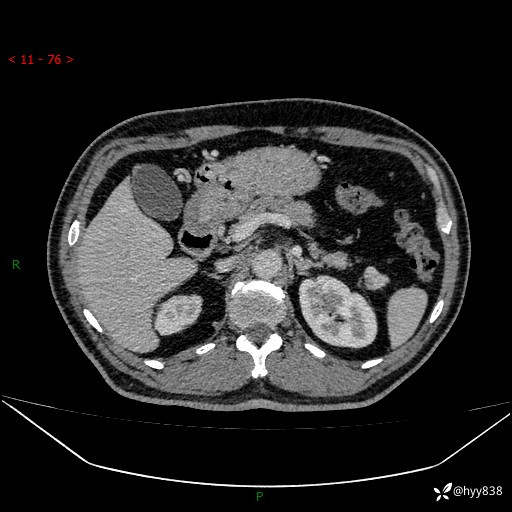

静脉期